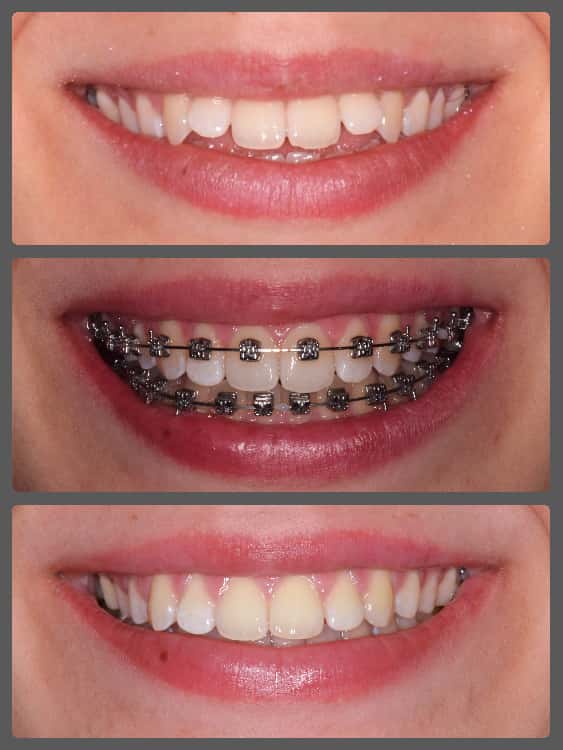

Szonja és szülei torlódott fogazata miatt kerestek fel engem a Semmelweis Egyetemen. Az omega formájú, szűk fogívek mellett enyhe mélyharapást és disztálharapást is diagnosztizáltam nála. Alsó-felső hagyományos készüléket ragasztottunk Szonja fogaira, a mélyharapását harapásemelők segítségével korrigáltam, míg a disztálharapás megoldására intermaxilláris gumihúzást alkalmaztunk a fogszabályzó kezelés során. Bár Szonjának szüksége volt egy kis ösztönzésre, ami a gumihordást illeti, mégis rövid idő alatt értünk el gyönyörű eredményt. Látható, hogy a megfelelő diagnózis felállítását követően, helyes technikákat alkalmazva hagyományos készülékkel is nagyon szép eredményt lehet elérni, ráadásul belátható időn belül! Szonja kezelése 17 hónapig tartott.